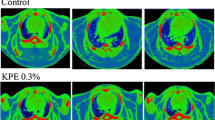

The number of small adipocytes was increased and the number of large adipocytes was decreased in the subcutaneous (Figure 1), perirenal (Figure 2), and mesenteric (Figure 3) adipocyte tissues in the KCL group compared with in the control and acetic acid groups. The number of large adipocytes was greater in the acetic acid group than in the control group. The DNA content, as an index of the number of cells, in the subcutaneous adipose tissue was significantly increased in the KCL group than in the control and acetic acid groups.

Effect of orally administered Kurozu concentrated liquid (KCL) on cell size in white adipose tissue. Adipocytes are shown in paraffin sections of subcutaneous (a) adipose tissue (scale bar: 100 μm). The profile of the distribution of the cell size of adipocytes from subcutaneous (b) adipose tissue. Values are means with standard errors for 7 rats per group. Different characters indicate significant differences at *P < 0.05, **P < 0.01.

Effect of orally administered Kurozu concentrated liquid (KCL) on cell size in white adipose tissue. Adipocytes are shown in paraffin sections of perirenal (a) adipose tissue (scale bar: 100 μm). The profile of the distribution of the cell size of adipocytes from perirenal (b) adipose tissue. Values are means with standard errors for 7 rats per group. Different characters indicate significant differences at *P < 0.05, **P < 0.01.

Effect of orally administered Kurozu concentrated liquid (KCL) on cell size in white adipose tissue. Adipocytes are shown in paraffin sections of and mesenteric (a) adipose tissue (scale bar: 100 μm). The profile of the distribution of the cell size of adipocytes from mesenteric (b) adipose tissue. Values are means with standard errors for 7 rats per group. Different characters indicate significant differences at *P < 0.05, **P < 0.01.

In the present study, the average size of adipocytes was significantly smaller in the subcutaneous and perirenal adipose tissues in the KCL group than in the control and acetic acid groups, despite the fact that KCL administration did not change the adipose tissue mass. Reduction of adipocyte size is meaningful for preventing obesity because the enlargement of adipose tissue increased hypertrophy and hyperplasia can cause obesity [22]. The increase in adipocyte tissue mass in obese mice is characterized by an increase in adipocyte size up to a maximum size, followed by an increase in the number of adipocytes [23]. Hypertrophic adipocytes secrete growth factors that can trigger adipogenesis through hyperplasia, and excess secretion has been hypothesized to cause insulin resistance [5]. In the KCL group, the number of small adipocytes in the subcutaneous, perirenal, and mesenteric adipocyte tissues were increased while the number of large adipocytes was decreased. The DNA content reflects number of cells in the tissues. In the present study, DNA content in the subcutaneous adipose tissues in KCL group was significantly increased. Therefore, the adipose tissues in the KCL group possessed more small cells per a unit than the other groups. These changes in the adipocyte size distribution profile were beneficial in the prevention of obesity in SD rats and obese Zucker rats [2, 3]. These results indicate that KCL plays an important role in regulating the development of obesity.